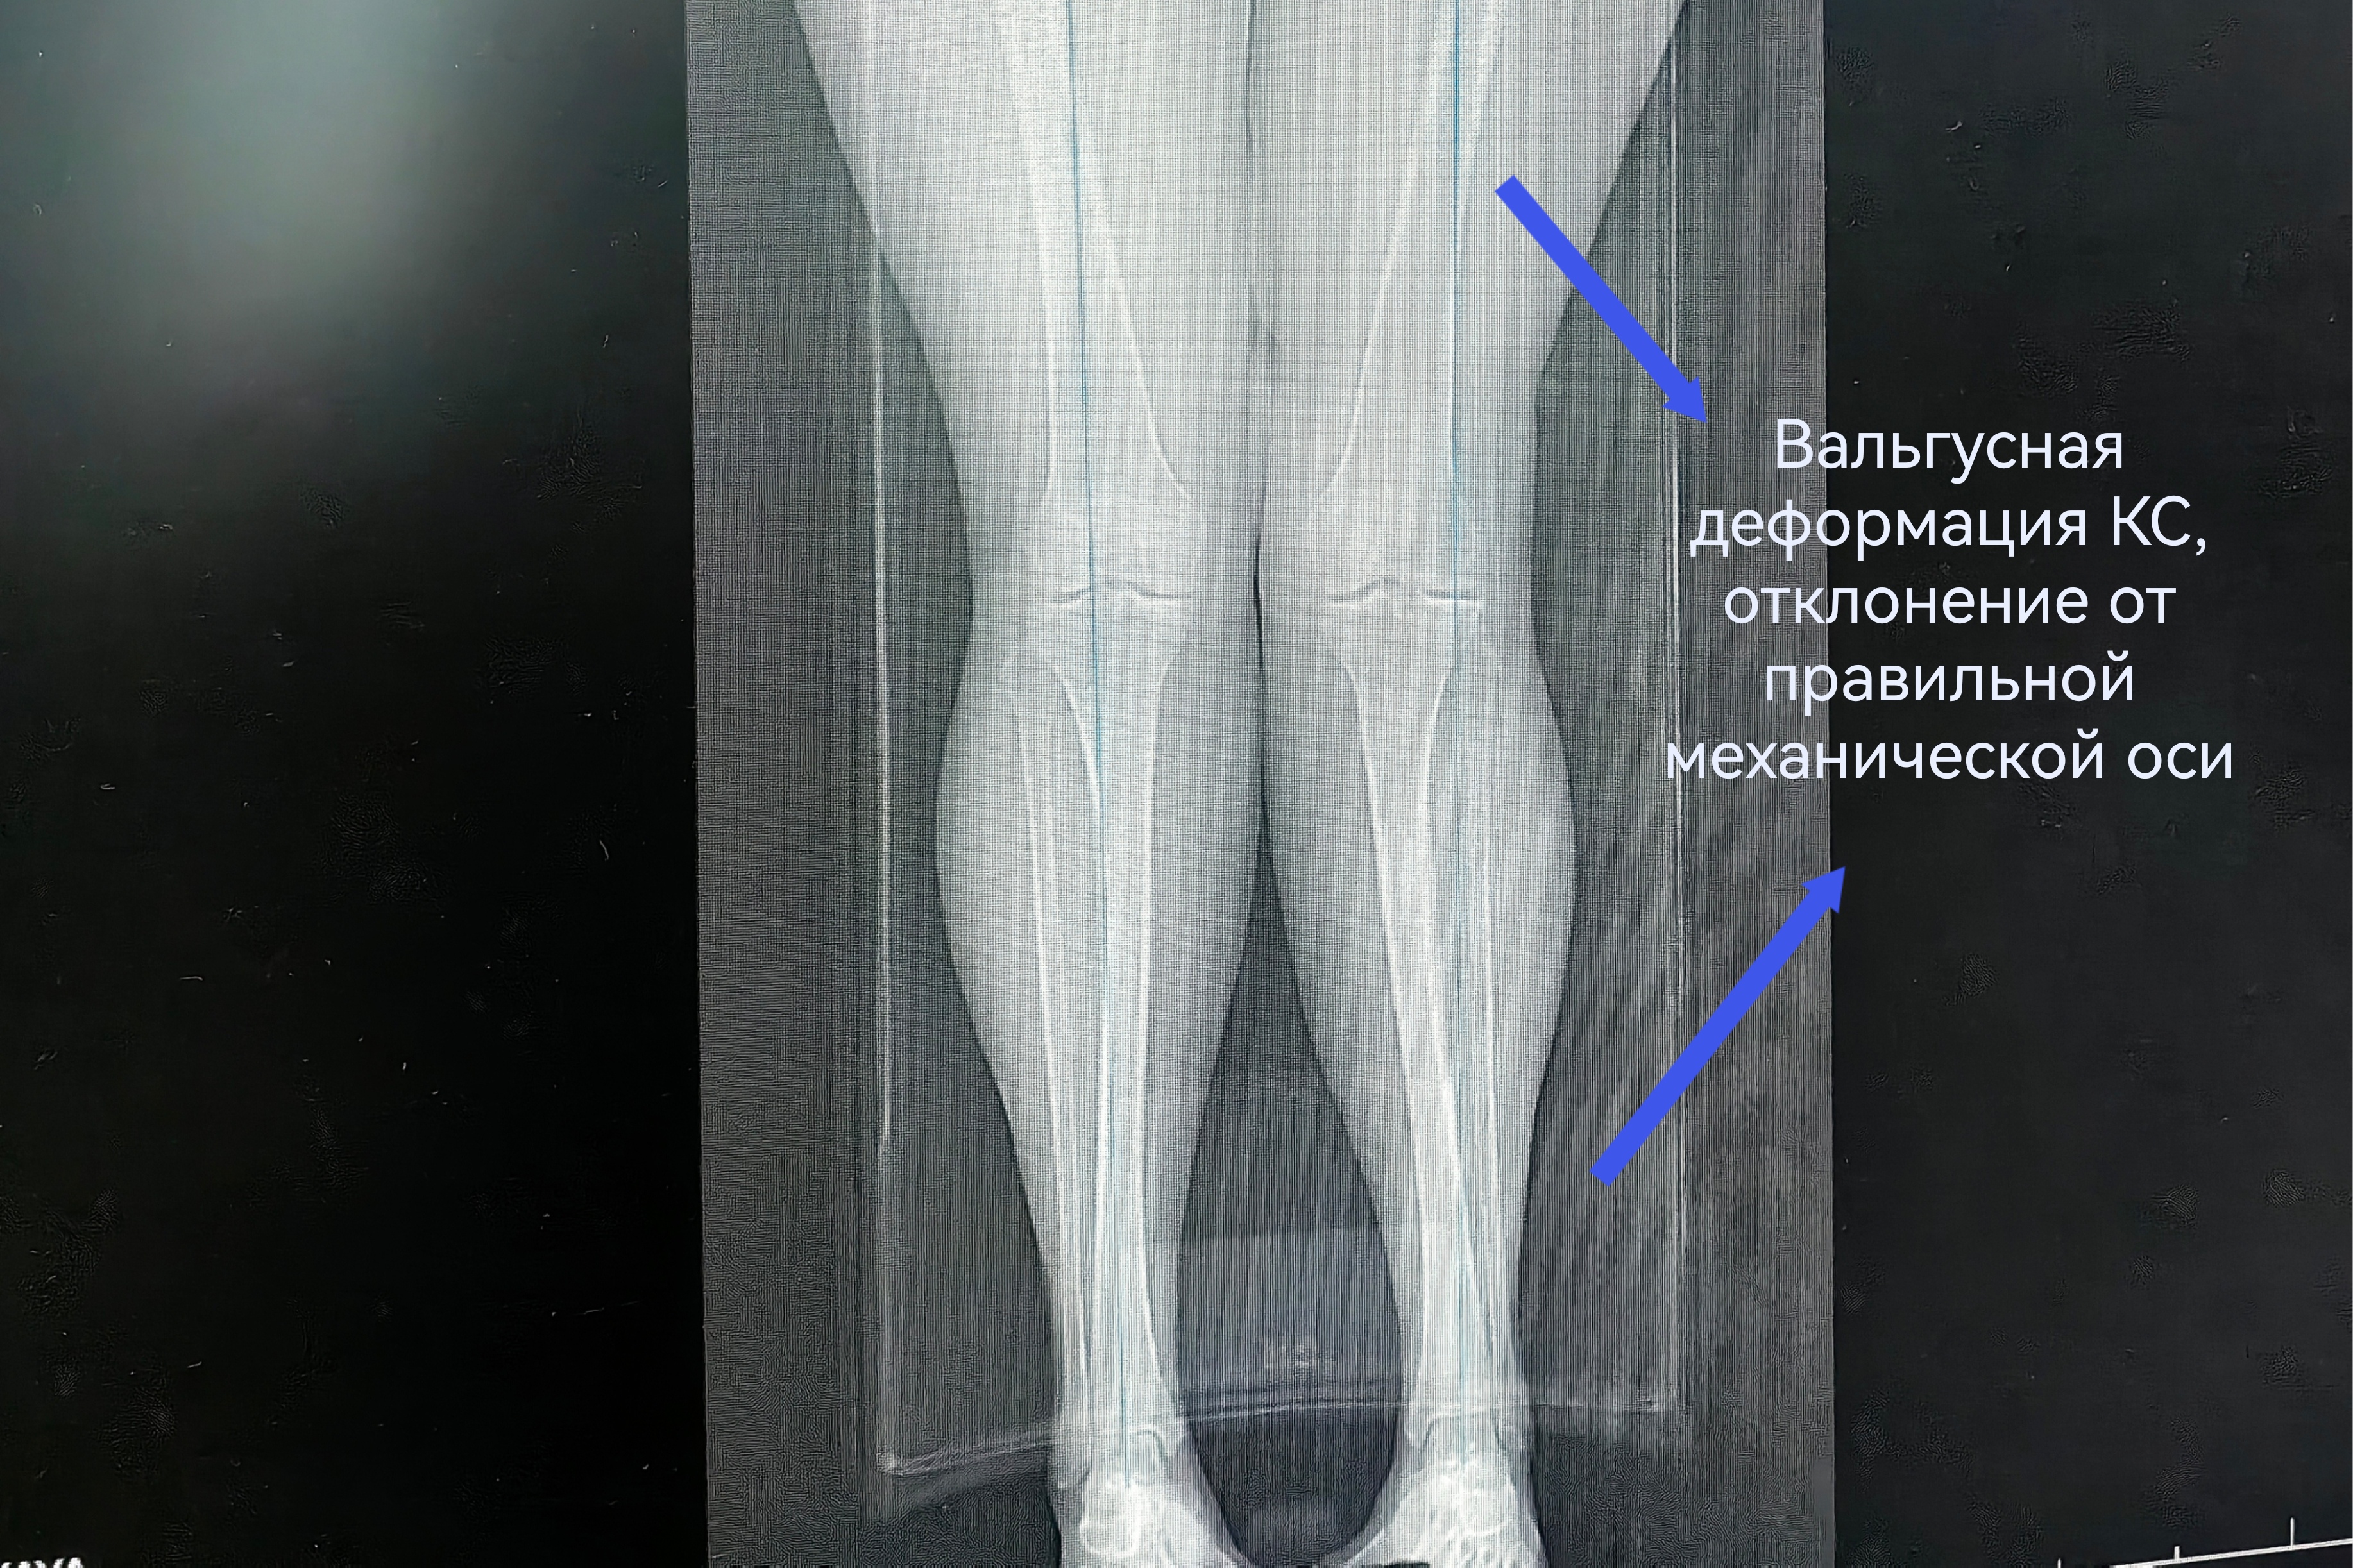

Чтобы избавиться от мучительной боли в колене, наша 55-летняя пациентка готова была избавиться от всего сустава. При госпитализации женщина настроилась на эндопротезирование. Однако травматологи-ортопеды выбрали другую тактику. При вальгусной деформации и деформирующем артрозе второй стадии коленный сустав оставался достаточно сохранным. Чтобы спасти его от замещения металлоконструкцией, была выполнена корригирующая остеотомия.

Суть операции – в исправлении нарушенной оси конечности. После перестроения и выравнивания костей голени нагрузка собственного веса смещается с пораженной части сустава на здоровую. Таким образом, болевой синдром регрессирует, а износ сустава замедляется.

Технически корригирующая остеотомия не представляет сложности. Непосредственно в операционной для опытного хирурга работы - на полчаса. А вот предварительное планирование – это целое исследование с множеством математических измерений и расчетов. В профессиональной среде говорят, что такая операция делается в основном в ординаторской. И это действительно так. До хирургического вмешательства врач должен предельно точно определить ось конечности, градус её отклонения и угол коррекции.

В случае с этой пациенткой ради сохранения коленного сустава пришлось пожертвовать 10 миллиметрами большеберцовой кости. Костный клин такого размера был удалён, чтобы вернуть конечность в правильную механическую ось. Небольшие размеры современных фиксаторов позволяют выполнять операции малотравматичным доступом – через 4-5-сантиметровый разрез.